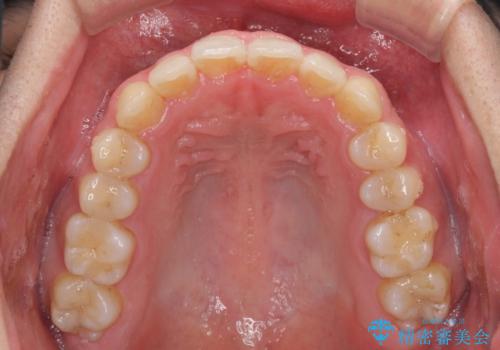

狭い歯列と前歯のデコボコ インビザラインによる矯正治療

- 上下前歯のデコボコを気にして来院された患者様です。

インビザラインによる上下歯列の拡大と、IPR(歯と歯の間を削る)にるスペースの獲得により、前歯のデコボコと狭い歯列を改善することとしました。

比較的軽度な歯列不正であったため、治療期間はそれほど長くはならないと予想されました。

しかしながら、あまりしっかりとマウスピースを装着していなかったため、思いの外期間が長引いてしまいました。

また、仕上がりの歯列にも若干の叢生が残ってしまいました。